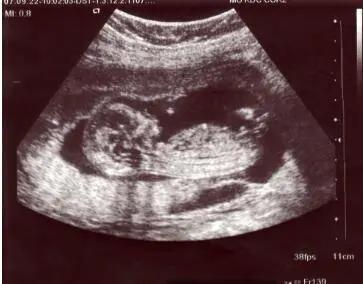

这样拖着,直到一个多月后,周欣发现自己怀孕了,新生命的到来,带给周欣带来的更多是不安和焦虑。

这个孩子会是谁的呢?

渐渐的,周欣放下了同学会那场遭遇带来的阴影,怀着一丝侥幸心理,开心的和丈夫一起期待宝宝的降临。

几个月后,女儿方芳的降临对于整个家带来了无尽的欢乐,方芳快快乐乐的长到了八岁,一家人也相安无事,尽享天伦。然而这样的幸福并没有持续多久,随着方芳被查出患有白血病,整个家的平静,被彻底打破了。